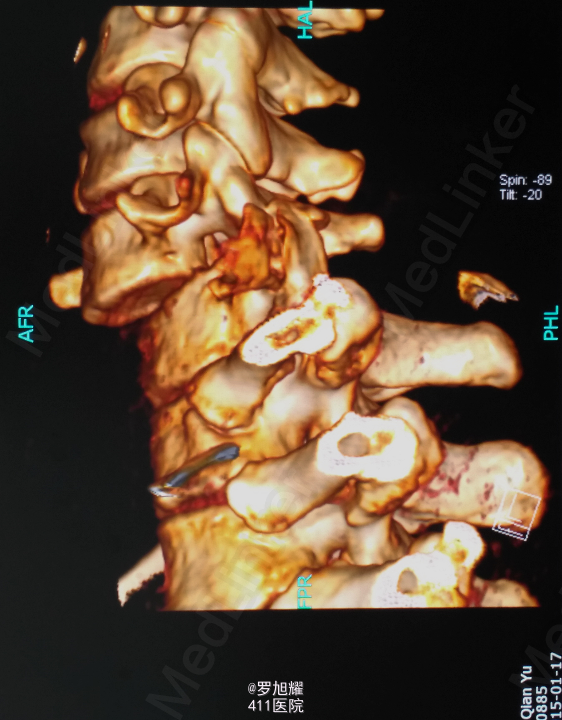

查体:双上肢前臂及以远感觉丧失,躯体自第二肋间平面以下感觉丧失。耸肩可,双侧三角肌、肱二三头肌肌力2级,腕关节屈伸、旋转及各指肌力0级。腱反射阴性,但球海绵体反射已经阳性。影像学检查示颈椎骨折脱位伴颈髓损伤。

诊断:颈6/7骨折脱位伴高位截瘫。处理:立即甲强龙冲击、脱水、保胃、营养神经治疗。首选治疗方案是颅骨牵引复位后前路融合固定,较后路稳定,出血也少,和家属谈话后开始颅骨牵引复位,4kg起步,每半小时增加1kg直至14kg,调整颈椎屈伸位,再加用手法牵引仍不能复位。改用备选方案,急诊行后路切开减压撬拨复位内固定,术后瘫痪症状部分改善。随访3月双上肢前臂及手部感觉恢复,仅双手掌尺侧及小指感觉障碍,双侧三角肌、肱二三头肌肌力4-5级,腕关节屈伸、旋转肌力左侧3级,右侧3-4级,但各指肌力仍0级。